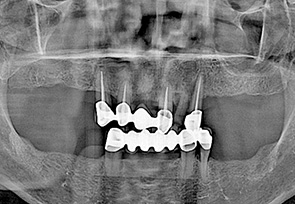

• before

• after